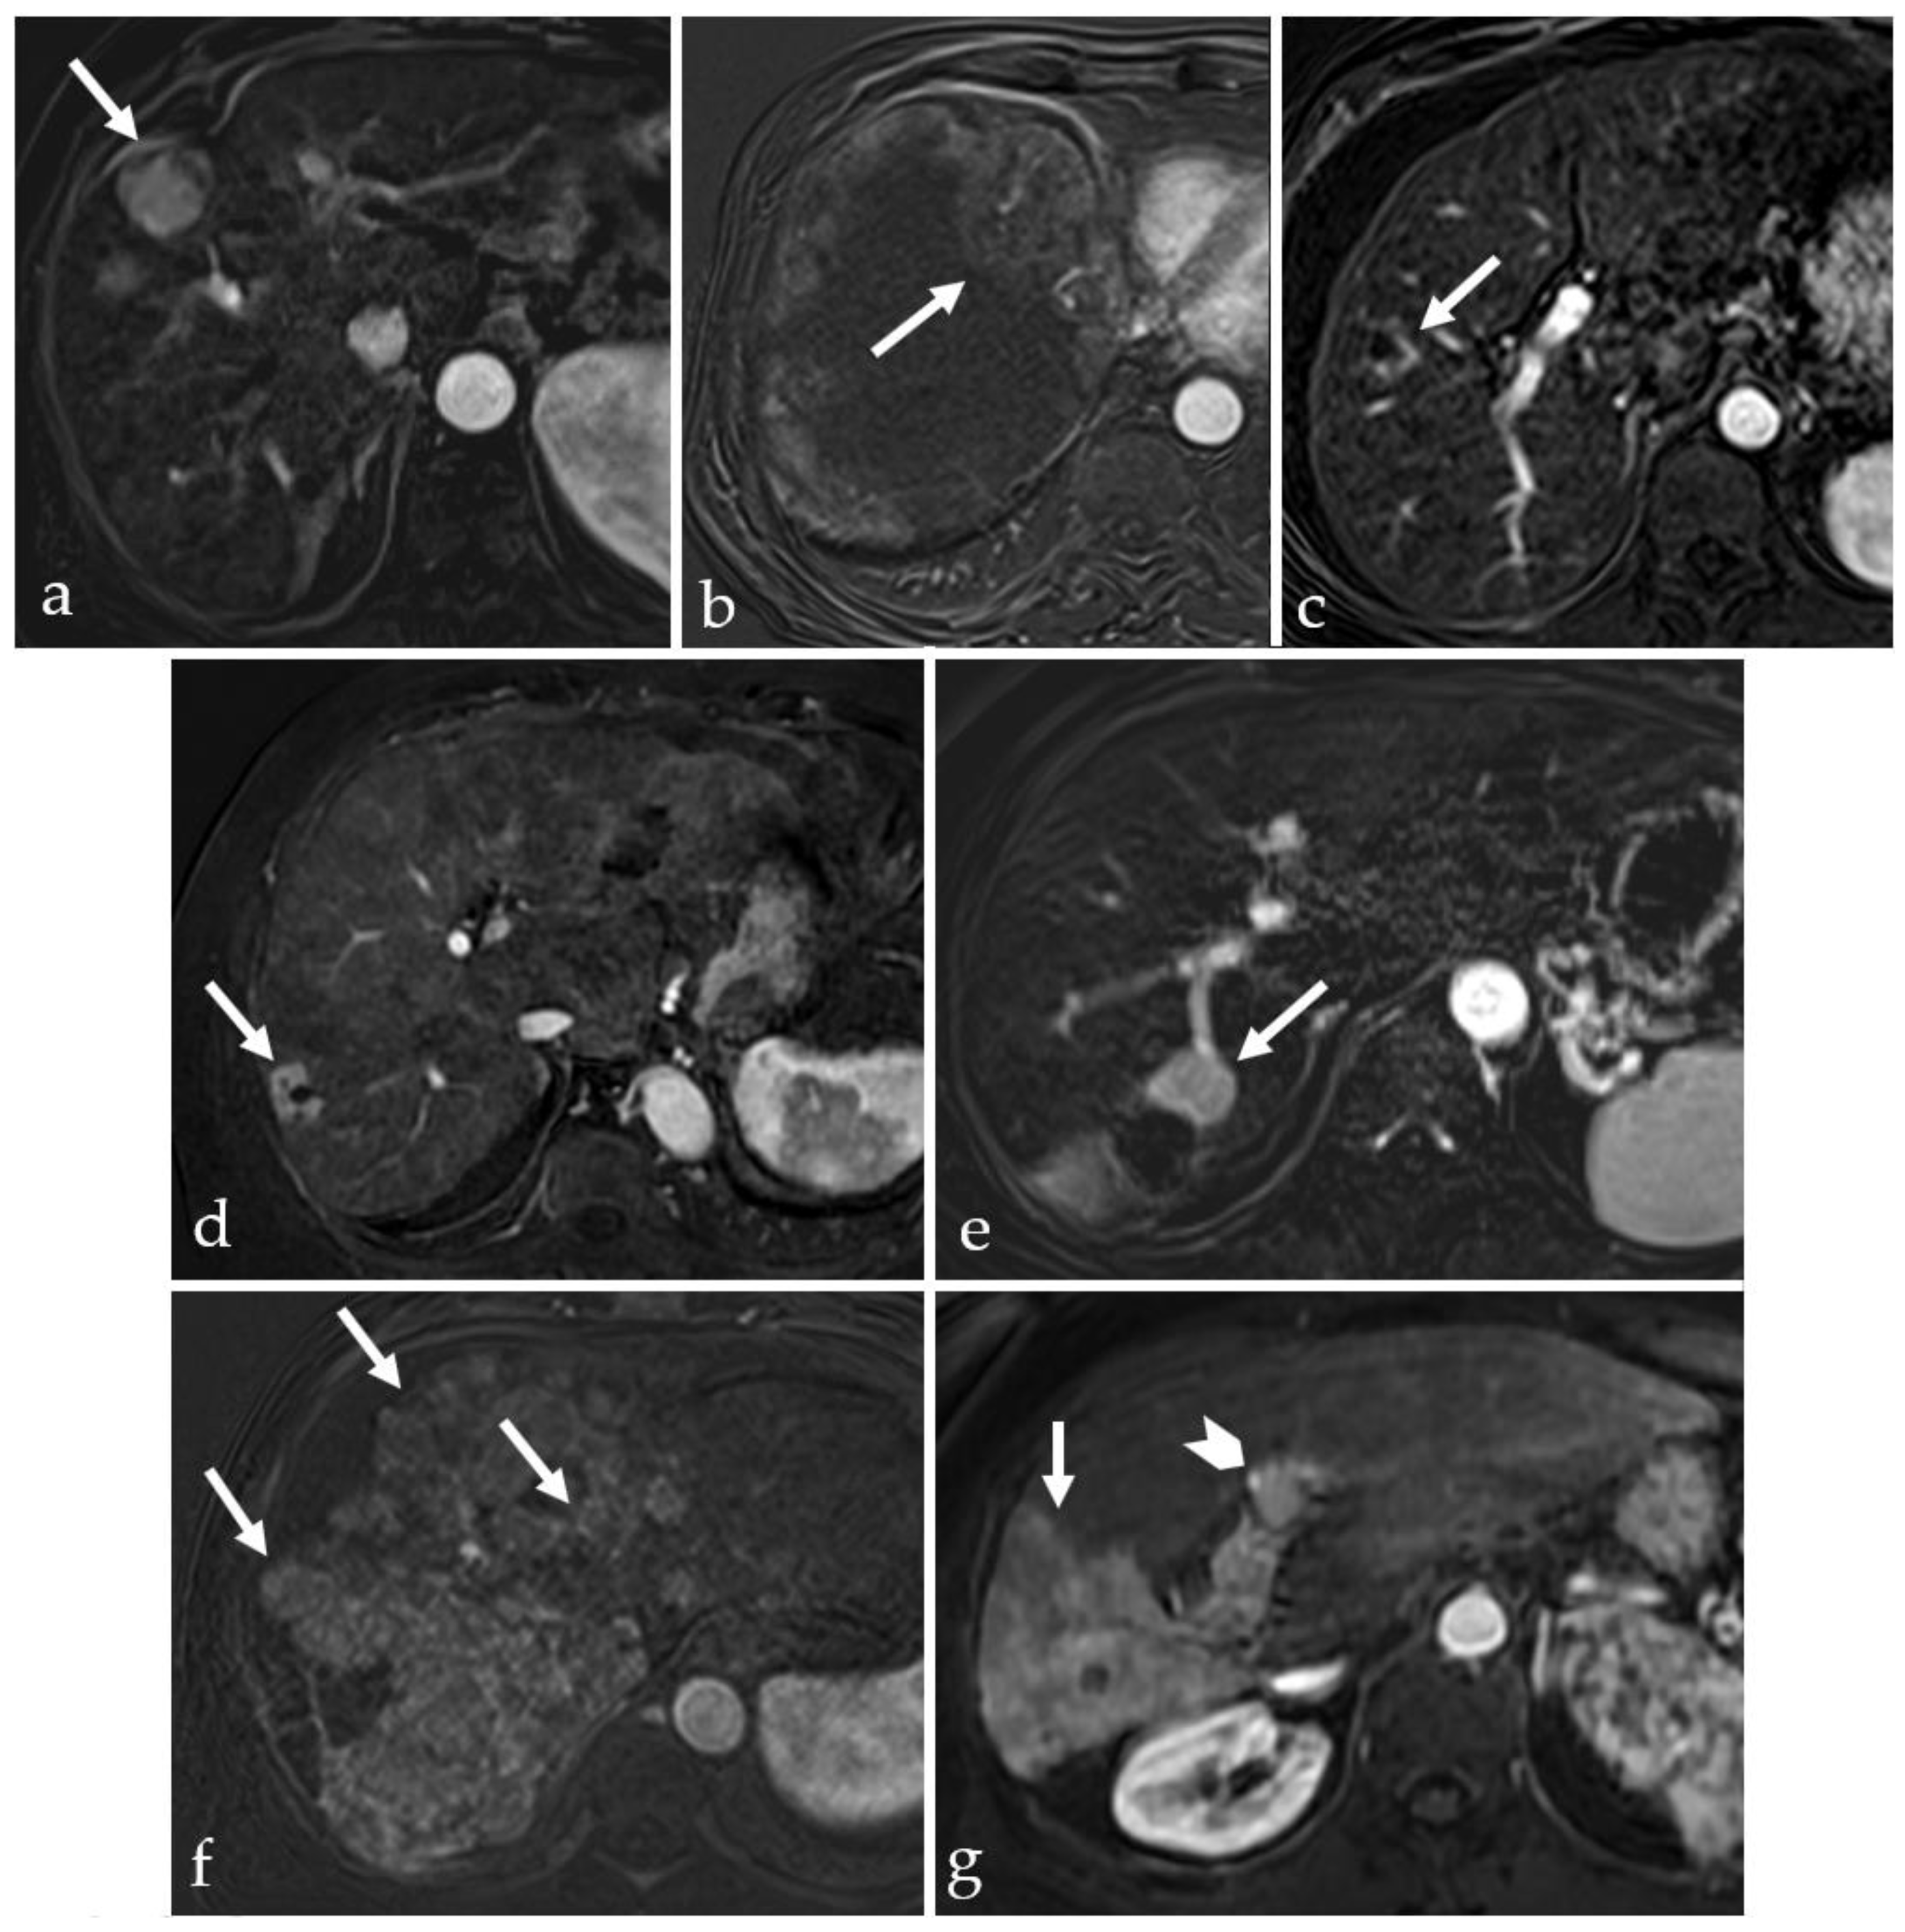

3.4. TACE-Associated Necrosis

3.5. Post-Treatment Imaging Features of Tumor Viability

| cTACE | 0-B | Combination of local chemotherapy and tumor devascularization | Vascular or biliary complications may occur Difficult in anatomical variants Postembolization syndrome may occur Poor response in hypovascular nodules | Coagulation and liquefactive necrosis (H- and hT1, H- and hT2) | 24–54% |

| DEB-TACE | 0-B | Superior chemotherapeutic effect Fewer adverse effects related to the chemotherapeutic drugs | Coagulation and liquefactive necrosis (H- and hT1, H- and hT2) | 33–61% | |